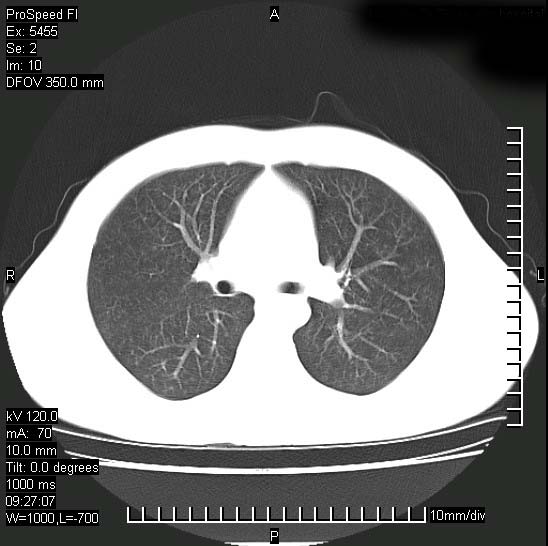

以下是引用zjzjr在2008-12-3 20:50:00的发言:[br]考虑泛细支气管肺炎,建议进一步检查除外肺出血性疾病如含铁血黄素沉着症、肺肾综合征等。

以下是引用zjzjr在2008-12-3 20:50:00的发言:[br]考虑泛细支气管肺炎,建议进一步检查除外肺出血性疾病如含铁血黄素沉着症、肺肾综合征等。

以下是引用光线在2008-12-3 20:19:00的发言:[br]双肺间质性改变。